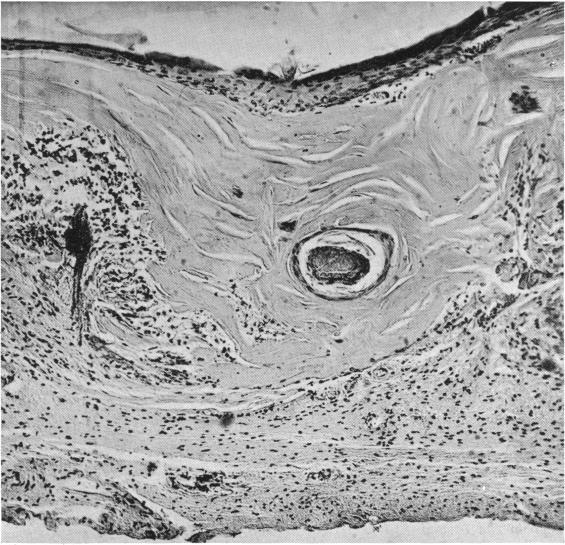

DERMOID CYSTS OF THE VERTEBRAL CANAL.

Ann Surg. 1939 Aug;110(2):273-84. doi: 10.1097/00000658-193908000-00008.